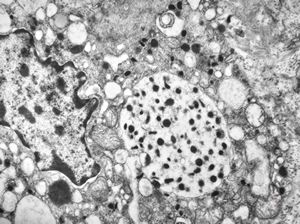

M, 38y. | pheochromocytoma